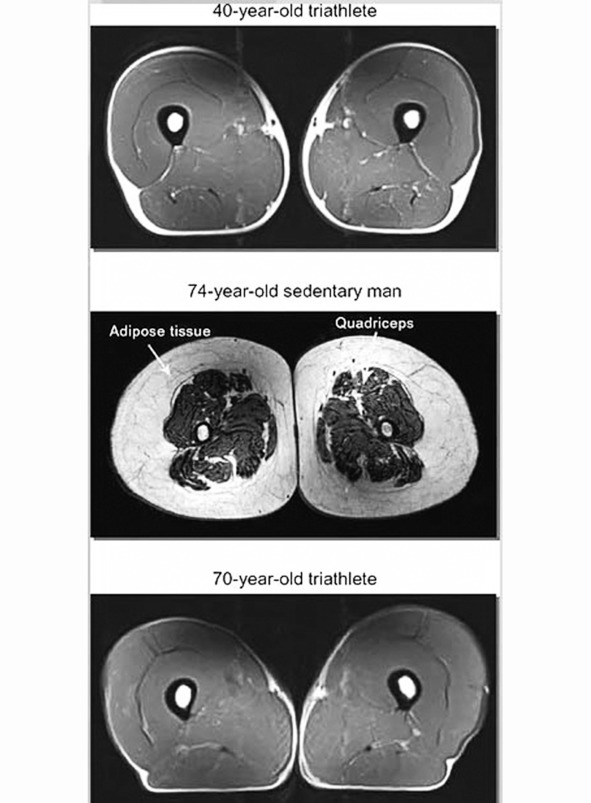

На верхнем снимке – нога 40-летнего спортсмена-троеборца

Посредине – 74-летний человек, который решил именно «докряхтеть» кое-как свою жизнь

И внизу – 70летний атлет

А теперь сложим эти два явления: свое мраморное от малоподвижного образа жизни мясо и саркопению. И получится совсем неаппетитная картиночка: в толще жировой и соединительной ткани тонкими ремешками-веревочками жалкие остатки мышц.